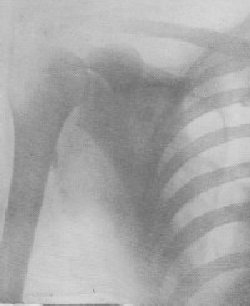

By courtesy of W. Scheidel & co., Chicago

Bullet, as detected by the X-Ray.

It was early discovered that the X-rays could penetrate light proof paper and fog a photographic plate. If the hand is placed so that the X-rays can pass through it before reaching the plate, the bones will obstruct the rays more than the plate, and that part of the plate beneath the bones will be less affected than the part next to the tissue. Thus by proper development of the plate an image of the bones of the hand will be seen. The same holds good for all other parts of the body. The usual method is to place the patient on a suitable table in a reclining position. The tube is so arranged that the rays will pass downward through the body of the patient. A photographic plate is then placed beneath that part which is to be photographed. With the earlier apparatus, a long exposure was required to take even a hand, but now very short exposures of the thickest parts of the body will be sufficient. The X-rays are used by the surgeon in detecting any fracture of the bones, dislocation of the joints, or the presence of a foreign body. Formerly, it was a difficult operation to probe for a bullet, but now the projectile can be exactly located with the X-ray. Swallowed coins and pins, often a source of the greatest anxiety to parents, need not be so much feared. A metal object is readily located in any part of the child's alimentary canal, and its progress can be kept track of as it moves through the system. Many deformities seen in the arm and wrist due to incorrect reduction of a fracture are now without excuse, because the X-ray will show wherever a bone is misplaced.